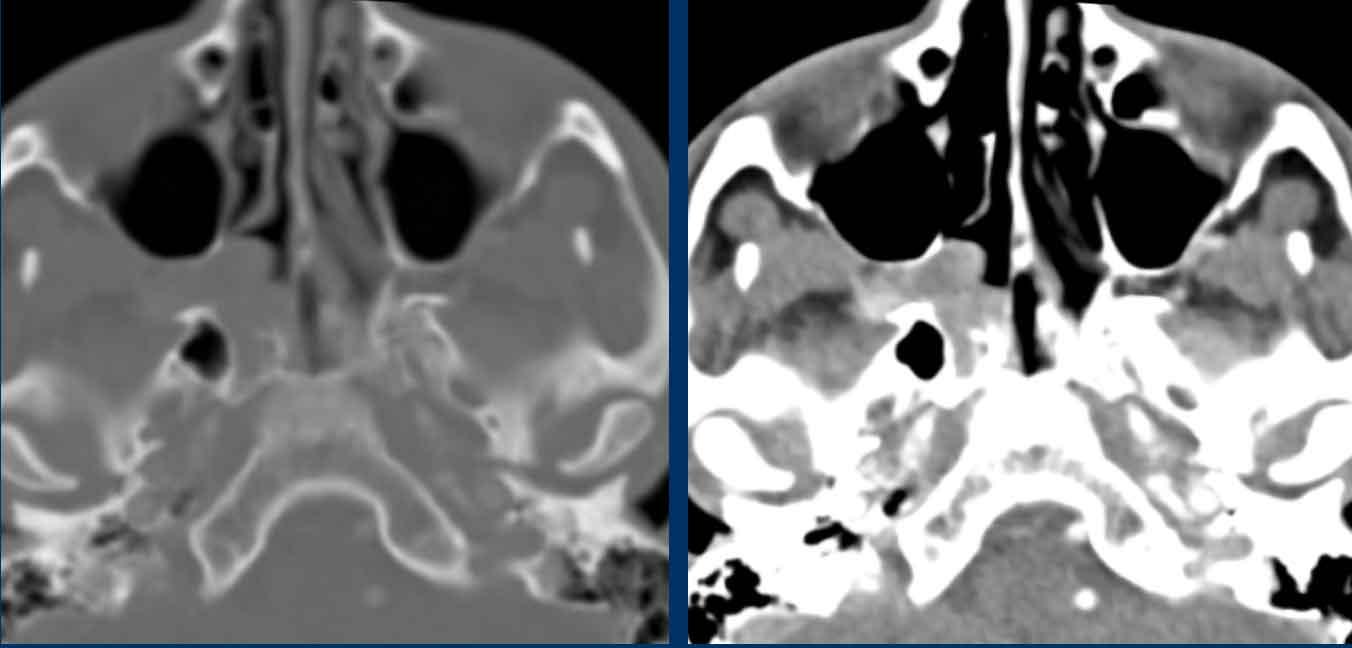

Bệnh nhân nữ 62 tuổi.

CT xoang được chỉ định bởi bác sĩ tai mũi họng. Thông tin lâm sàng: ‘viêm xoang một bên mạn tính’.

Hình ảnh

Có hình ảnh mờ đặc do mô mềm tại xoang hàm, xoang sàng và xoang trán bên phải (gọi là ‘kiểu tắc nghẽn phễu’).

Như đã đề cập, đây là một dấu hiệu cảnh báo.

Hãy quan sát các hình ảnh tiếp theo và cố gắng xác định liệu có tổn thương ác tính nào gây ra kiểu tắc nghẽn phễu này không (hay có nguyên nhân nào khác không?)

Có hình ảnh thấu quang quanh chóp răng tại vùng chân răng hàm lớn trên bên phải, gợi ý nhiễm trùng răng (đầu mũi tên đen).

So sánh với bên trái bình thường trên ảnh cắt ngang (đầu mũi tên trắng).

Thăm khám lâm sàng bổ sung đã loại trừ tổn thương ác tính.

Bệnh nhân được chuyển khám răng hàm mặt vì nhiễm trùng răng hoàn toàn có thể là nguyên nhân gây viêm xoang mạn tính một bên.

Lưu ý: Vì lý do này, việc bao gồm vùng xương hàm trên trong trường chụp của CT xoang là điều hết sức quan trọng.